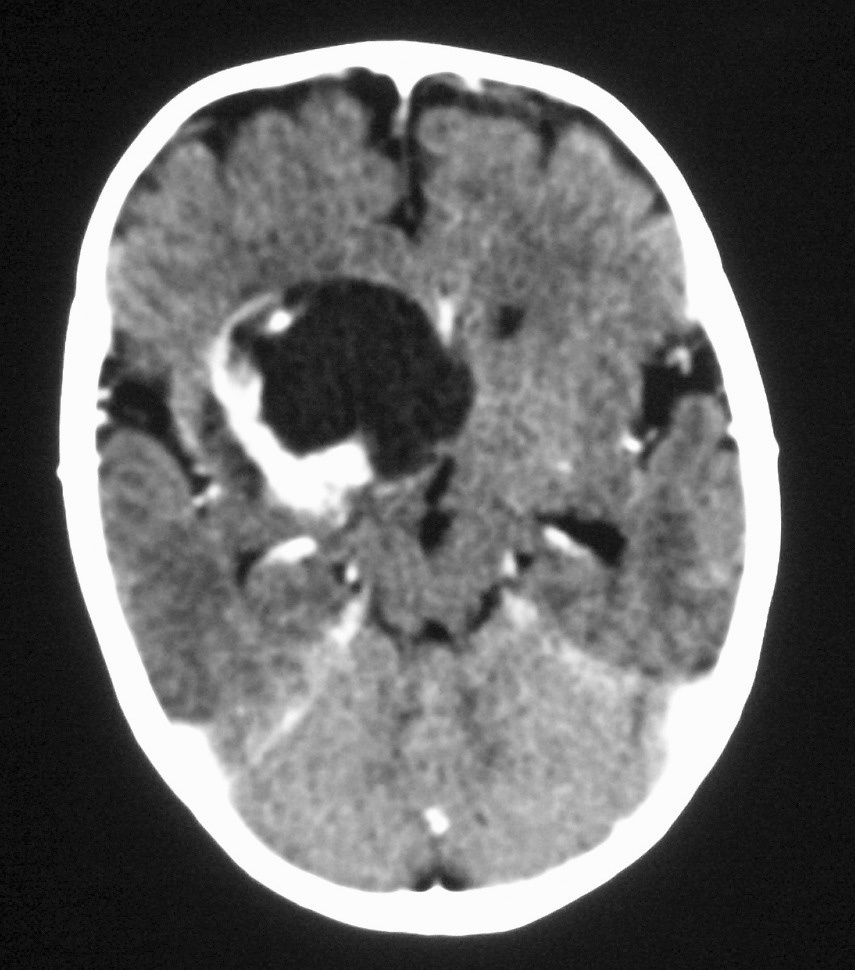

El tumor rabdoide se presentó en un niño de 5 meses estudiado por masa abdominal palpable y hematuria, con el antecedente de un hermano gemelo fallecido poco tiempo antes por tumor cerebral. El estudio con ecografía y TC abdominal demostró una masa renal sólida, heterogénea e hipodensa con poco realce. Se completó el estudio con ecografía transfontanelar y TC craneal identificando una masa cerebral sincrónica, intraaxial, frontal paramedial, sólido-quística con calcificaciones (fig. 7). No se conoció la histología del tumor cerebral por seguimiento del paciente en otro centro.

Fig. 7 Tumor rabdoide. Niño de 5 meses con hematuria y masa abdominal. (A) Ecografía abdominal. Corte longitudinal renal izquierdo. Masa sólida, heterogénea (M), bien delimitada en polo inferior de riñón izquierdo. (B) Tomografía computarizada abdominal con contraste intravenoso. Masa renal hipodensa, de aspecto infiltrativo, con crecimiento extrarrenal y tenue captación de contraste. (C) Tomografía computarizada craneal. Masa intraaxial, sólido-quística, fronto-temporal derecha, que desplaza la línea media, con un área de calcificación periférica.